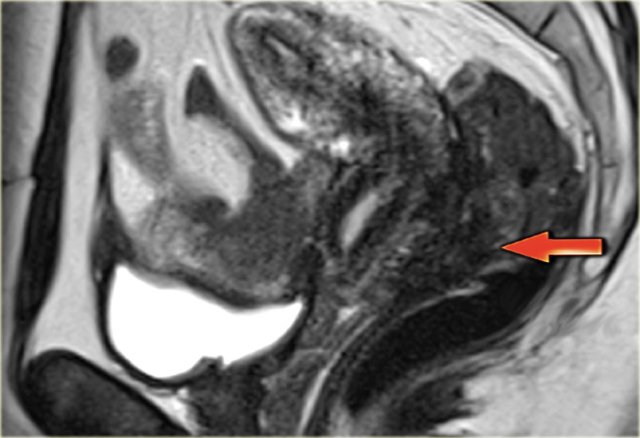

On transvaginal ultrasound, endometriomas may be seen as thick-walled

cysts with low level echoes.

On the left a transvaginal ultrasound image and the corresponding laparoscopic image during cystectomy.

On MRI, endometriomas present as solitary or multiple masses

with a homogeneous hyperintense signal intensity on T1- and T1-fatsat sequences.

The T1-fatsat helps differentiate endometriomas from mature cystic teratomas, which usually contain fat.

On T2WI, endometriomas may range from having a low signal intensity (also known as shading) to an intermediate or high signal intensity.

The low signal intensity reflects the hemoconcentration of a cyst.

Endometriomas generally have a thick, fibrous capsule with low signal intensity on T2, caused by hemosiderin-laden macrophages (figure).